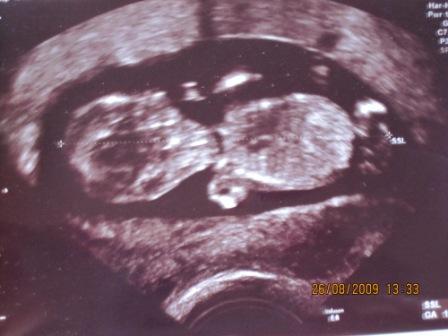

Erstmal muss ich sagen dass ich etwas enttäuscht von meinem FA war, da er mich am Montag sehr schnell "abgefertigt" hatte. Das kenn ich so gar nicht vom ihm, schließlich war seine letzte VU ganze 7 Wochen her. Er hatte mir erklärt dass er wenig Zeit hat, weil es sein erster Tag nach 3 Wochen Urlaub war und es über die Sommerferien hier wohl einen Baby Boom gab weil plötzlich wohl aussergewöhnlich viele schwanger sind. Hab ich zwar Verständniss für, aber ich dachte dass ich wenigstens meinen Mutterpass bekomme, aber nee den gibts erst in 2 Wochen. Grummel, dann bin ich schon 15. Woche find ich eigentlich viel zu spät. Naja Ultraschall hat er gemacht, Gummibärchen ist schon richtig groß geworden: 5,6cm Bildchen hänge ich an, ich hab auch ein 3D Bild bekommen, versuche ich auch mal hochzuladen LG Jana